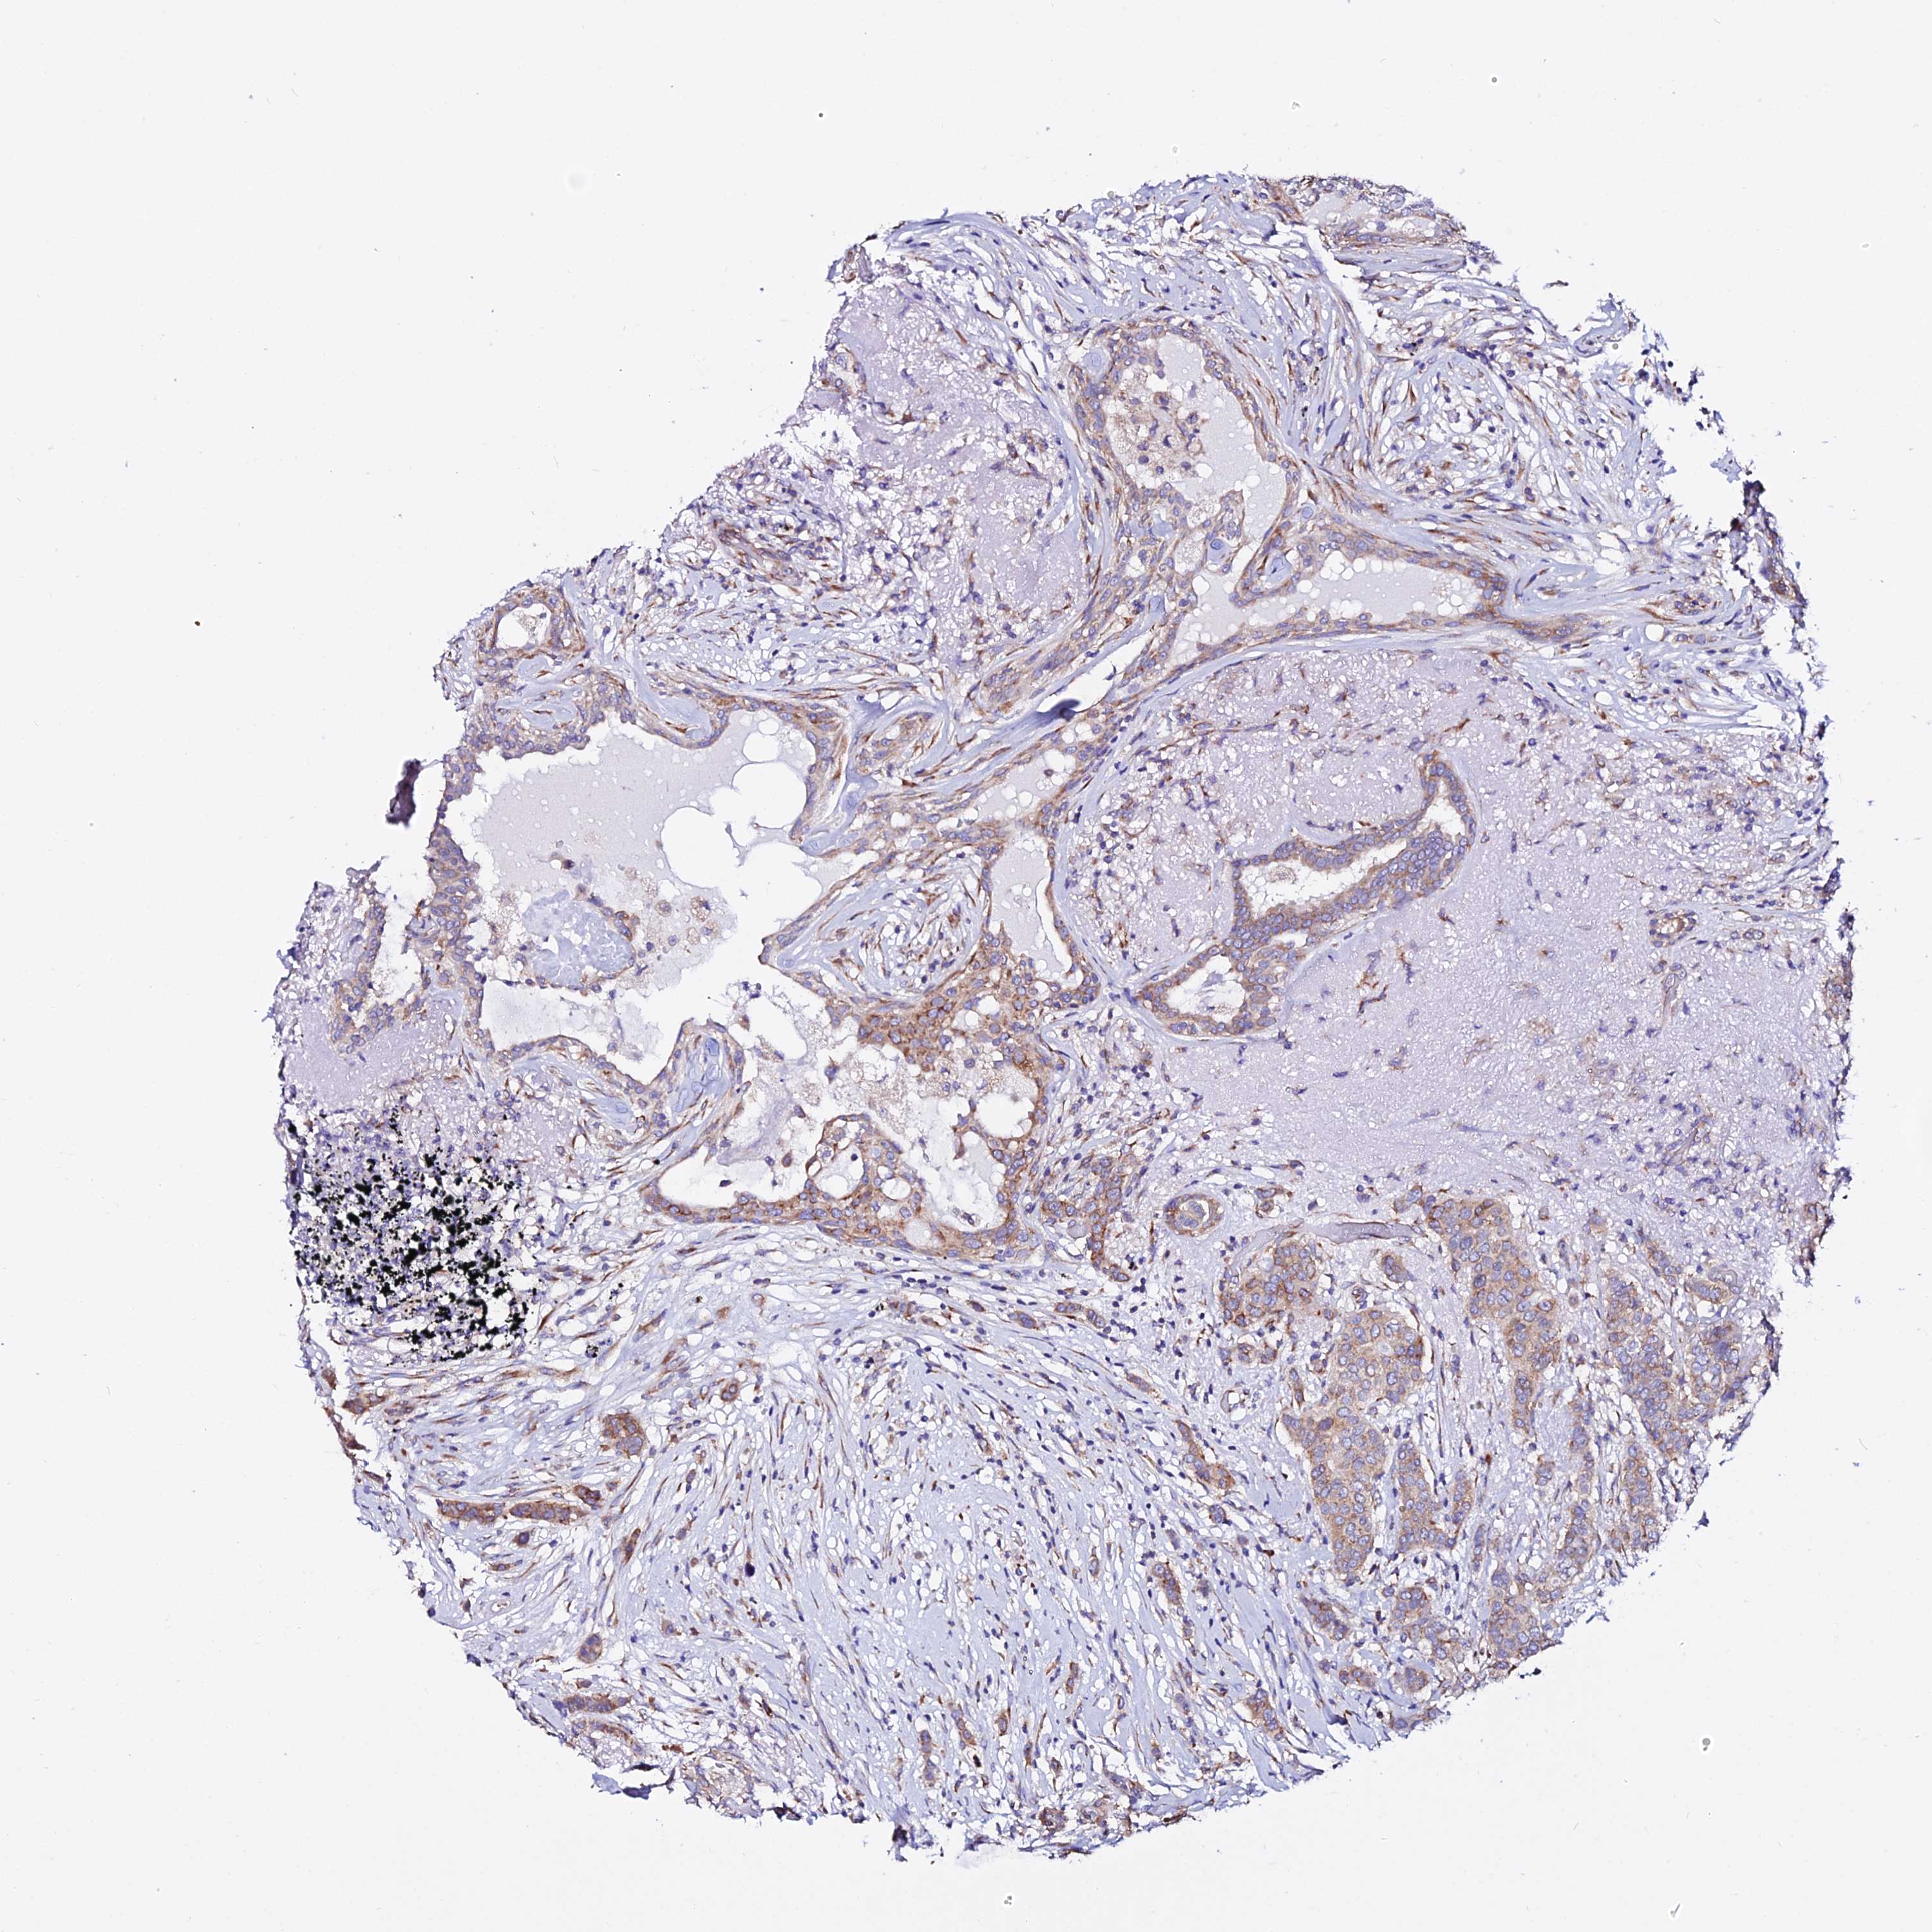

CANCER BREAST CANCER Show tissue menu

BRCA TCGA BRCA VALIDATION PROTEIN EXPRESSION